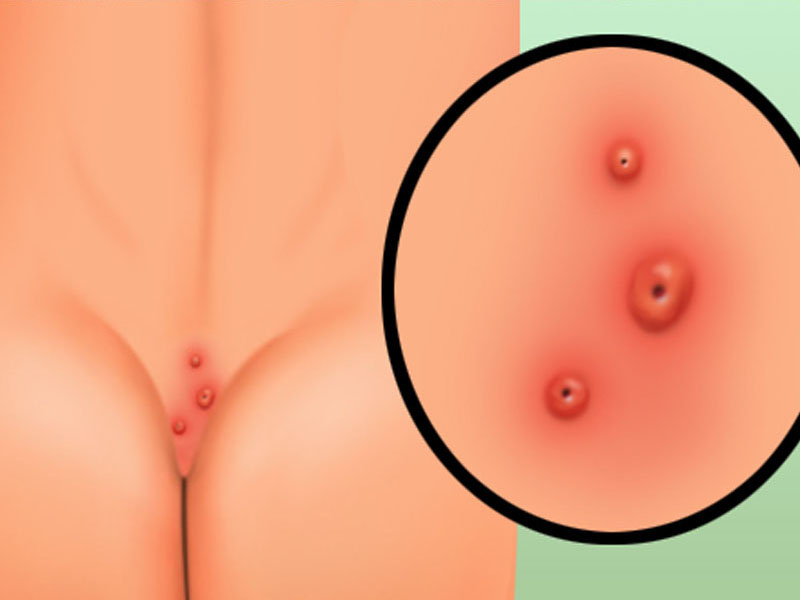

Pilonidal Cyst

Pilonidal disease is an infection of the skin in the region of the 'buttock crease'. It creates a cavity (cyst) below the skin surface.